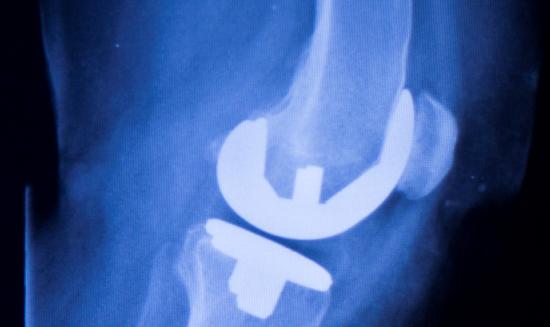

骨科植入器材是指被植入人体内,用于取代、修复、补充、填充或辅助治疗受损伤骨骼的器材的统称。它们主要由金属材料、生物陶瓷材料、高分子材料等制成,可以长期植入人体,对人体的生命和健康有着重大影响。骨科植入......

骨科植入医疗器械,指的是通过手术植入人体,可以起到替代、支撑人体骨骼或者可以定位修复骨骼、关节、软骨等组织的器材材料,主要包括骨接合植入物及关节植入物,如接骨板、接骨螺钉、髓内钉、脊柱内固定植入物、人......